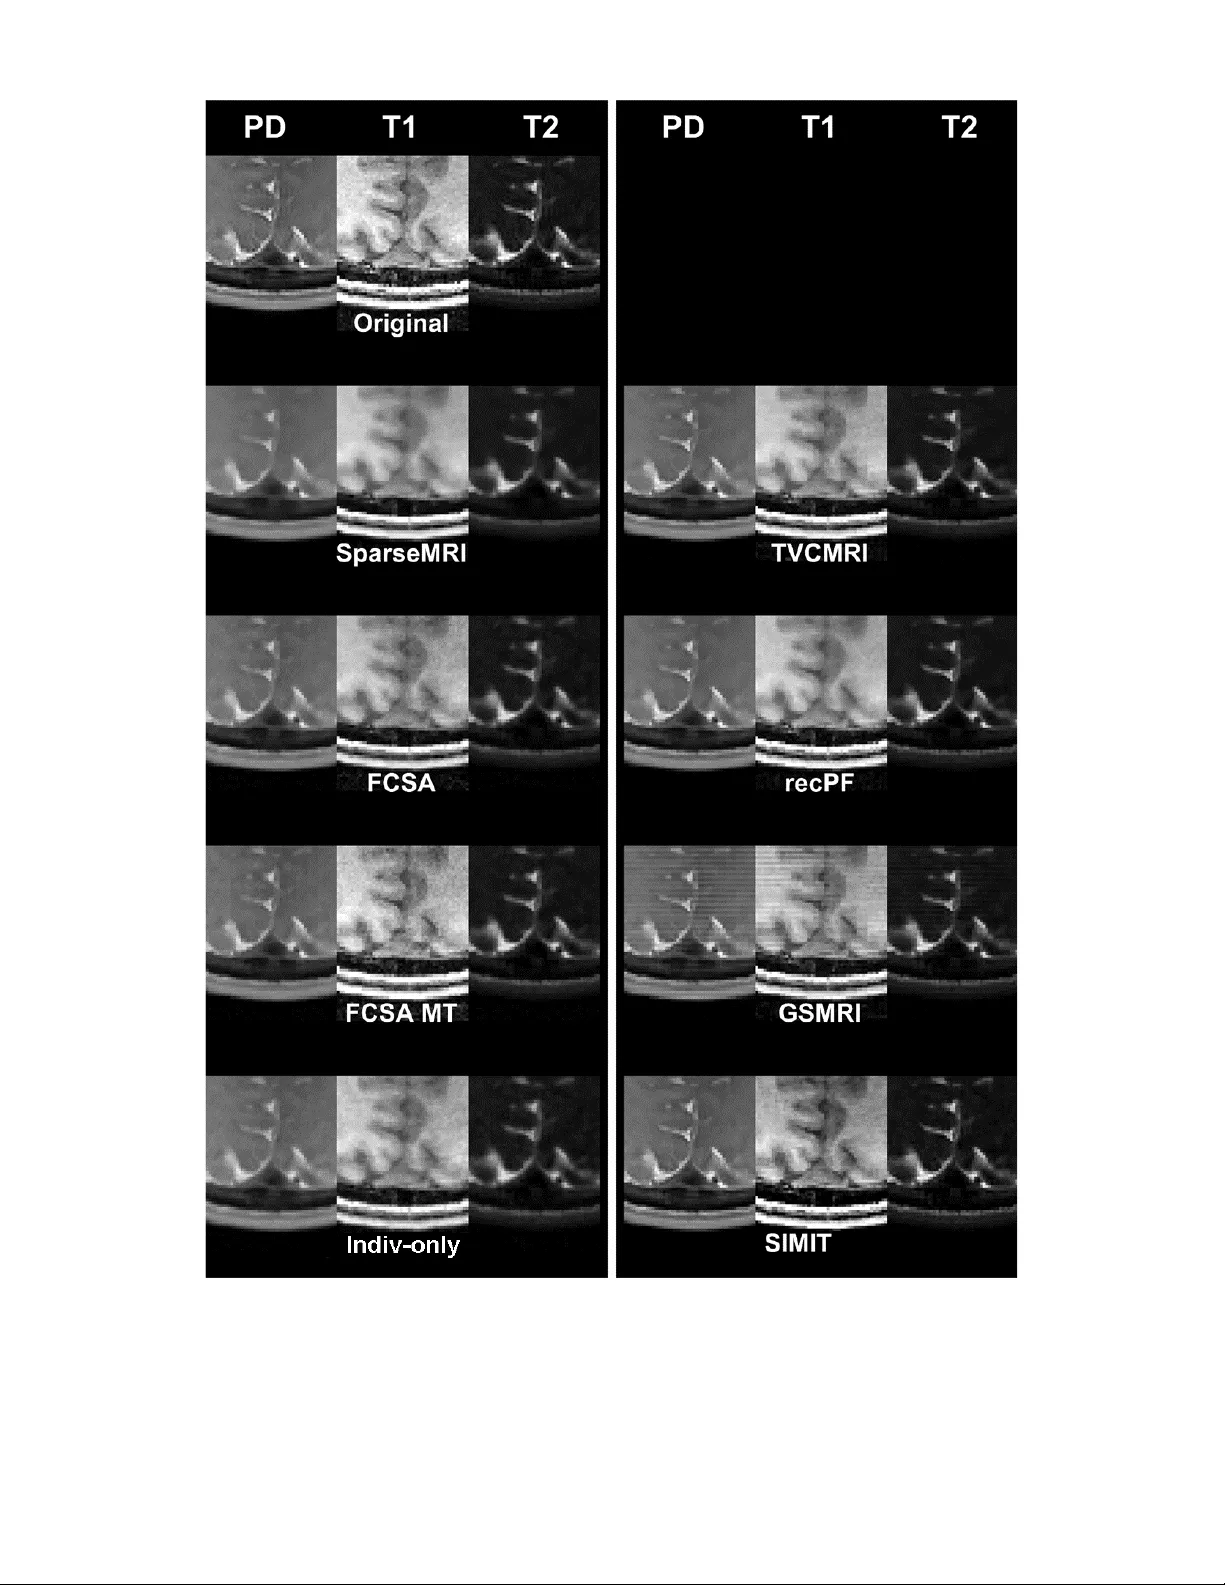

Simultaneous use of Individual and Joint Regularization Terms in Compressive Sensing: Joint Reconstruction of Multi-Channel Multi-Contrast MRI Acquisitions

Multi-contrast images are commonly acquired together to maximize complementary diagnostic information, albeit at the expense of longer scan times. A time-efficient strategy to acquire high-quality multi-contrast images is to accelerate individual seq…